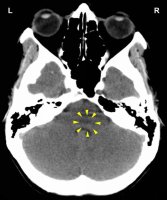

DEVELOPMENT AND FUNCTION OF THE MOUTH AND PHARYNX SUBMUCOSA: The mouth is the opening of the alimentary canal and the place where the digestion (secretory quality) and absorption (absorptive quality) of food starts. The tongue is an accessory digestive organ that aids in chewing and swallowing. Through chewing, food is broken into small pieces. Saliva produced in the salivary glands moistens the food bolus to make swallowing easier. The salivary glands are located in several parts of the mouth. The largest salivary glands are the parotid glands in front of the ears, the sublingual glands underneath the tongue, and the submandibular glands beneath the lower jaw. The pharynx connects the mouth and nasal cavities with the trachea and the larynx. The nasopharynx, located in the back of the nose, extends to the upper surface of the palate which forms the roof of the mouth; the oropharynx is at the very back of the mouth. On both sides of the pharynx lie the tonsils. Branching off the pharynx is the esophagus that carries food from the mouth to the stomach. The submucosa of the mouth and pharynx (including the lips, gums, palate, tongue, salivary glands, tonsils, and throat) consists of intestinal cylinder epithelium, originates from the endoderm and is therefore controlled from the brainstem.

CONFLICT-ACTIVE PHASE: Starting with the DHS, during the conflict-active phase cells in the submucosa of the mouth or pharynx proliferate proportionally to the intensity of the conflict. The biological purpose of the additional cells is to better insalivate a morsel in order to absorb (right half) or expel (left half) it faster. Salivation is stimulated by the autonomic nervous system. This is why the secretion of saliva increases with the smell of “mouth-watering” food. In the English language, “salivating” and “drooling” are synonyms for “craving” for something or someone desirable.

With prolonged conflict activity a flat growth (absorptive type) develops in the submucosa of the mouth. In the palate, salivary glands, tonsils, pharynx, and throat it can also take a cauliflower-shaped form (secretory type). If the papillae of the tongue that contain the taste buds are affected, the additional cells provide an enhanced sense of taste in order to be able to analyze (see sensory quality) the “morsel” (compare with hypersensitivity to taste related to the posterior third of the tongue).

Adenoids in the nasopharynx form as a result of a hanging conflict, that is, when the “scent morsel”-conflict cannot be resolved in time (compare with polyps in the paranasal sinuses). If the tonsils are affected, this causes tonsillar hypertrophy, or enlarged tonsils. Since the tonsils and the nasopharynx share the same brain relay, nasal polyps and enlarged tonsils often occur together.